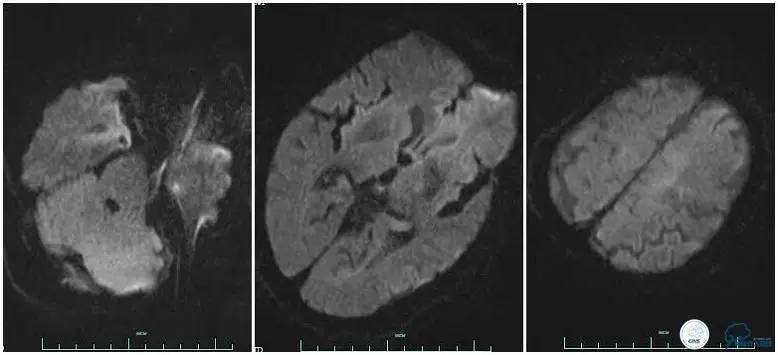

辅助检查:血常规、生化、凝血功能未见明显异常,心电图:窦性心律,ST-T改变;头颅CT平扫:未见明显出血。头颅MRI:未见新鲜梗塞灶;头颅MRA:双侧大脑前动脉远端缺如。

术前头颅MRI。

术后复查头颅MRI。

3.该患者治疗过程中存在一定不足,患者右侧肢体偏瘫症状明显,取栓过程中因血管扭曲未能优先处理左侧大脑前动脉。虽然术后血流完全再通,但复查头颅MRI左侧大脑前供血区域仍有大片梗死,右侧上肢肌力恢复不理想。